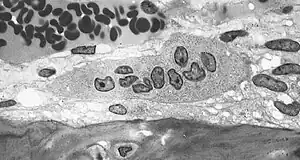

An osteoclast is a large multinucleated cell and human osteoclasts on bone typically have four nuclei[5] and are 150–200 µm in diameter. When osteoclast-inducing cytokines are used to convert macrophages to osteoclasts, very large cells that may reach 100 µm in diameter occur. These may have dozens of nuclei, and typically express major osteoclast proteins but have significant differences from cells in living bone because of the not-natural substrate.[6][7] The size of the multinucleated assembled osteoclast allows it to focus the ion transport, protein secretory and vesicular transport capabilities of many macrophages on a localized area of bone.

In bone, osteoclasts are found in pits in the bone surface which are called resorption bays, or Howship's lacunae. Osteoclasts are characterized by a cytoplasm with a homogeneous, "foamy" appearance. This appearance is due to a high concentration of vesicles and vacuoles. These vacuoles include lysosomes filled with acid phosphatase. This permits characterization of osteoclasts by their staining for high expression of tartrate resistant acid phosphatase (TRAP) and cathepsin K. Osteoclast rough endoplasmic reticulum is sparse, and the Golgi complex is extensive.[8][9][10]

At a site of active bone resorption, the osteoclast forms a specialized cell membrane, the "ruffled border", that opposes the surface of the bone tissue. This extensively folded or ruffled border facilitates bone removal by dramatically increasing the cell surface for secretion and uptake of the resorption compartment contents and is a morphologic characteristic of an osteoclast that is actively resorbing bone.